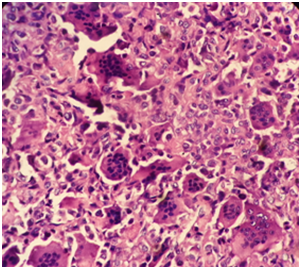

A 35 year old female, presented with complaints of back pain since one year, difficulty while walking, and weakness and loss of sensation of bilateral lower limb since six weeks. She was investigated and started on Antitubercular treatment (ATT) for the same problem in the other hospital on the basis of MRI report which suggested Pott’s disease. Symptoms persisted even after completion of six months course of ATT. After two months, ATT was started again from local center without improvement in the symptoms. So, the patient presented to the hospital for the aggravation of symptoms. On examination, she had tenderness over lower dorsal region with muscle power of grade 2 in the right lower limb and grade 1 in the left lower limb. There was bilateral decreased sensation from T12 dermatome and below and complete loss of sensation from L4 dermatome and below. Previous diagnosis was challenged and Fine needle aspiration cytology (FNAC) of the lesion was done. FNAC of the lesion revealed singly scattered round to ovoid cells with numerous osteoclastic giant cells suggestive of Giant cell lesion (Figure 1). On the basis of FNAC report, CT scan of dorsal spine was suggested which showed collapsed D12 vertebral body with the lytic lesion at vertebral body and bilateral pedicles. Patient had undergone total en-bloc spondylectomy D11, D12, L1 vertebra and tumor. Then, the specimen was sent for histopathological examination. On gross examination, multiple pieces of bony fragments along with soft tissue were received. On microscopy, prominent and diffuse osteoclastic giant cell component without any malignant changes were seen (Figure 2).

Figure 2 Giant cell tumour composed of round to ovoid cells in stroma with numerous multinucleated giant cells (X40).